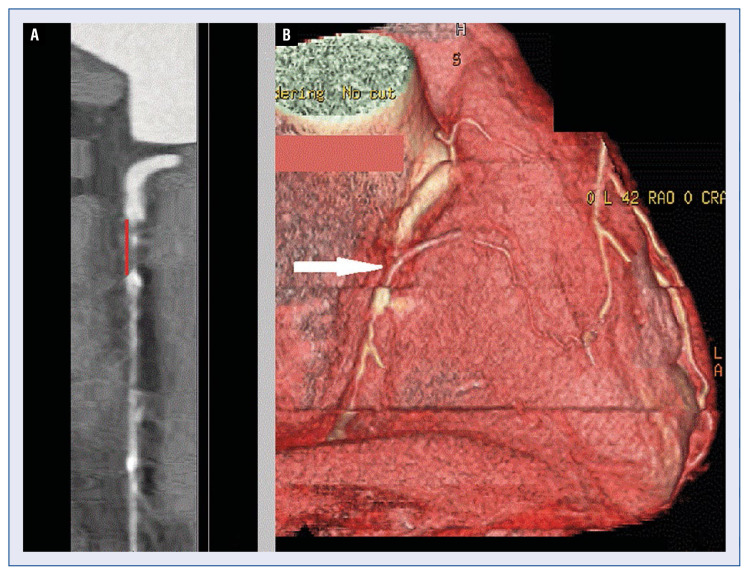

Coronary chronic total occlusions (CTOs) are a common finding on coronary angiograms of patients with coronary artery disease, with an incidence ranging from 15% to 25%. Despite this high incidence, the proper treatment strategy in those patients often remains unclear. There are some observational studies suggesting that successful revascularization of a CTO can reduce angina symptoms, improve quality of life, improve the left ventricular ejection fraction, and lower mortality. However, not all patients will benefit from revascularization. Pre-procedural assessment of left ventricular function, ischemic burden, and viability seems to be crucial for a good outcome of the revascularization. The aim of this review is to compare currently available non-invasive imaging modalities with regard to utility in evaluation of patients with CTOs.